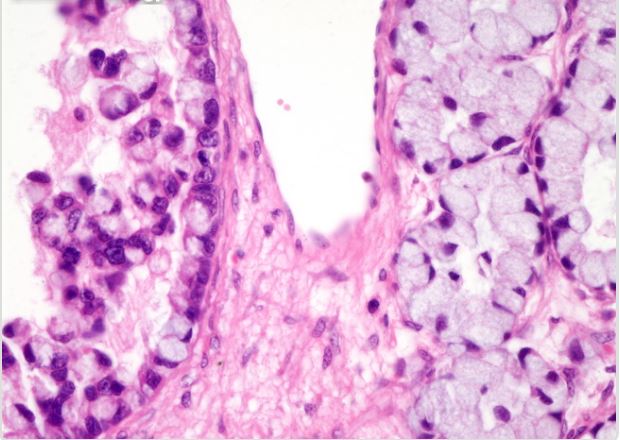

We consider two binary histopathology classification tasks, both framed as “cancer” vs. “non cancer”. The first dataset is the Ovarian Cancer & Subtypes Histopathology dataset111https://www.kaggle.com/datasets/bitsnpieces/ovarian-cancer-and-subtypes-dataset-histopathology, which contains digital pathology patches extracted from hematoxylin and eosin (H&E) stained ovarian tissue slides. We group the available subtypes into a single positive class (ovarian cancer) and use benign or non tumoral tissue as the negative class.

The second dataset is a subset of the LC25000 dataset222https://www.kaggle.com/andrewmvd/lung-and-colon-cancer-histopathological-images, which contains colon histopathology images with normal and tumoral samples. We select only colon images and map them to a binary label (cancer vs. non cancer). Representative examples of ovarian and colon patches for both classes (Figure 2).